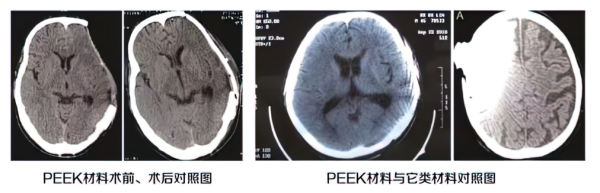

聚醚醚酮(PEEK)材料:聚醚醚酮是目前性能最接近人体骨骼的临床颅骨修补材料。利用计算机辅助设计和制造技术,结合3D打印建模技术,能够完美的重建颅骨缺损,恢复自然的颅骨外形。

4聚醚醚酮(PEEK)材料

● 优点:计算机个性化定制材料,性能接近人体骨,质地坚固,无受力凹陷;MRI/CT等影像学检查安全,无伪影,重物感小,无冷热温差感,持久恢复人体颅骨曲线,材料稳定。

● 缺点:价格较高,工艺复杂,订制流程略长。